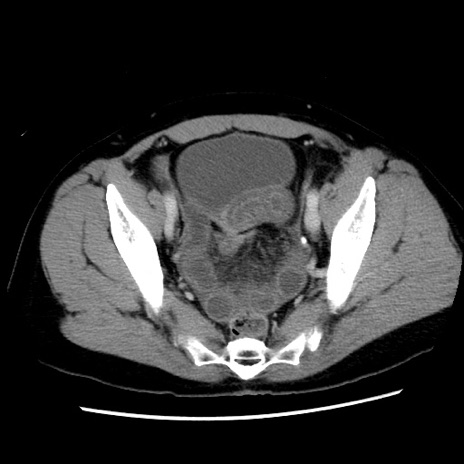

冠状断像

【症例】 50歳代女性

【主訴】 腹痛

【現病歴】前日生レバーを食べた。今朝に排便あり。 昼前に突然発症の腹痛を生じ、当院救急外来を受診した。

【既往歴】 子宮筋腫にてで子宮全摘後

【身体所見】 意識清明、腹部:平坦、軟、下腹部やや左を中心に圧痛・反跳痛あり、筋性防御あり

【データ】WBC 7800、CRP 0.07